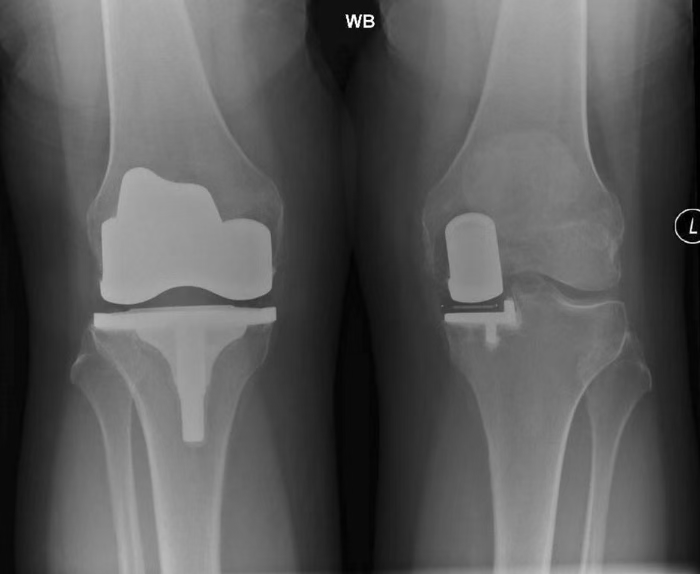

What used to be a straightforward choice based on rigid inclusion criteria has evolved into a precision medicine decision. The classic Kozinn & Scott standards — age >60, weight <82 kg, and low activity — are relics of the past.

With advanced prosthesis design, highly cross-linked polyethylene (HXLPE), and robotic-assisted navigation, the boundaries between UKA and TKA have dramatically shifted.

When UKA Is the Smarter Choice

UKA (Unicompartmental Knee Arthroplasty) is no longer reserved for the frail or sedentary.

It is a biomechanically conservative, function-preserving solution for the right patient profile.